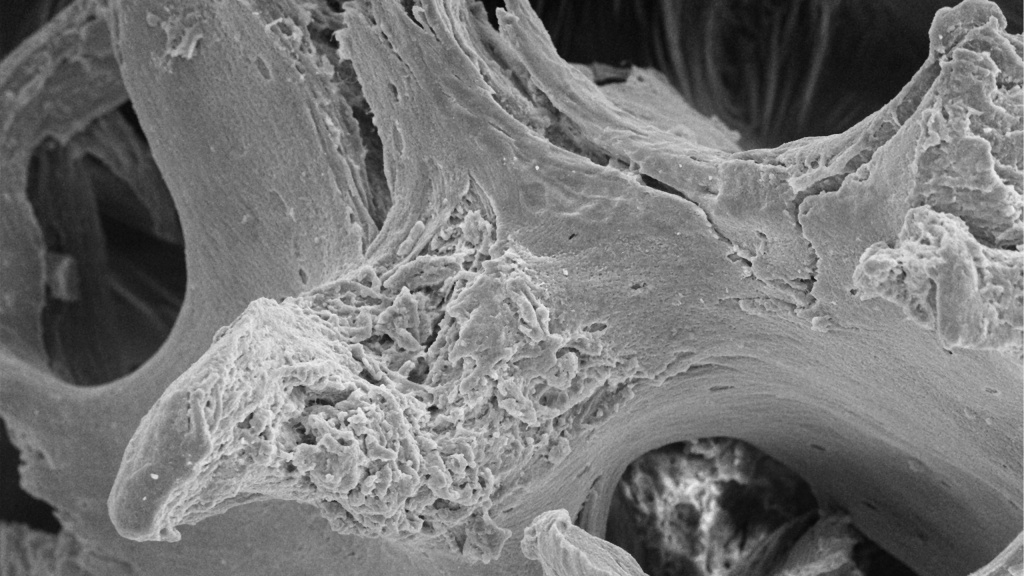

Технология ОСТЕОМАТРИКС. Там, где действительно нужна кость